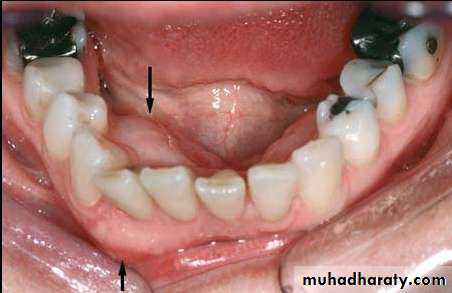

• 7. Flexiform unicystic ameloblastoma: Children between 10-19 years Typically in the mandible .

• 80% ,the cyst enclose the crown of impacted .

• severely displaced mandibular 3rd

• molar

• Unilocular radio-lucency

• 8. Peripheral ameloblastoma.

• These tumors are extraosseous and therefore occupy the lamina propria underneath the surface epithelium but outside of the bone.• Histologically, these lesions have the same features as the intraosseous forms of the tumor

• Patients respond well to local surgical excision.